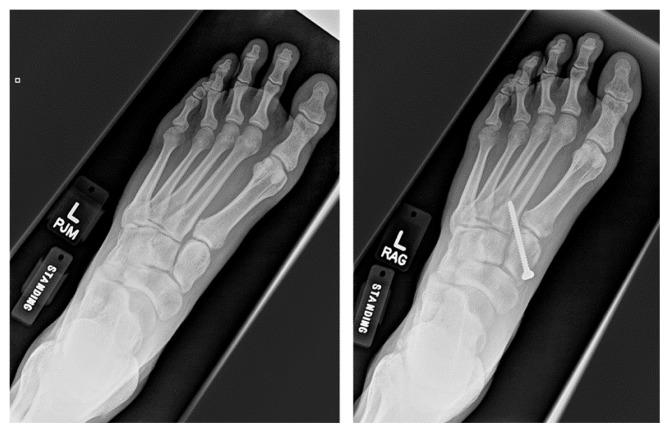

A Lisfranc injury can be a devastating injury in athletes, and if inadequately treated, may lead to chronic pain and loss of function. The purpose of this study was to determine the rate and time until return to sport after surgical fixation for a ligamentous Lisfranc injury. We hypothesized that open reduction and screw fixation of a ligamentous Lisfranc injury can be a successful treatment in the athletic population and allow patients to return to sport at close to their preinjury level of play.

METHODS

All patients who were analyzed underwent repair of a ligamentous Lisfranc injury with open reduction and screw fixation by a single surgeon, were between 18 - 40 years old at time of their final follow up, and were identified as being an athlete (either recreational or competitive). Eligible patients were given a questionnaire that included if they were able to return to sport, time until return to sport, subjective percentage of pre-injury level of play, current pain (0 - 10), and complications.